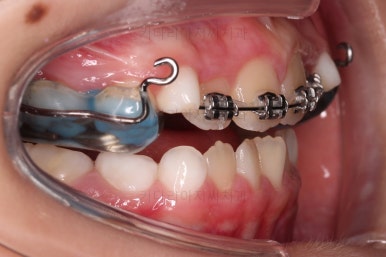

마찬가지로 초진 시 입안의 모습이에요.

아래 앞니가 윗니보다 앞에 있는 "반대교합" 즉, 거꾸로 물려있는 상황이었고요.

어금니 쪽을 보시면(왼쪽 위 사진) 윗니 어금니도 아래 어금니보다 안쪽으로 들어와 있는 "어금니 반대교합"도 있는 상황이었어요.

즉, 윗니가 있는 위턱뼈가 3차원적으로 작은 상황이었던거죠.

이렇게 아랫니들이 윗니보다 앞으로 나와있는 형태의 부정교합을 "앵글씨 3급" 부정교합이라고 합니다.

입 안에는 이런 장치가 들어가요.

착탈식은 아니고 부착형입니다.

앞니를 일부러 붕 띄워주며 위턱의 가로폭을 확장시켜주는 악궁확장장치도 부착이 되었어요.

어떻게 식사를 하냐며 걱정하시는 보호자분들이 계시지만 씹는 면을 편평하게 아랫니와 맞춰주었기 때문에 기존의 부정교합인 상태보다 오히려 식사가 잘 될 수 있으니 염려 안하셔도 됩니다.